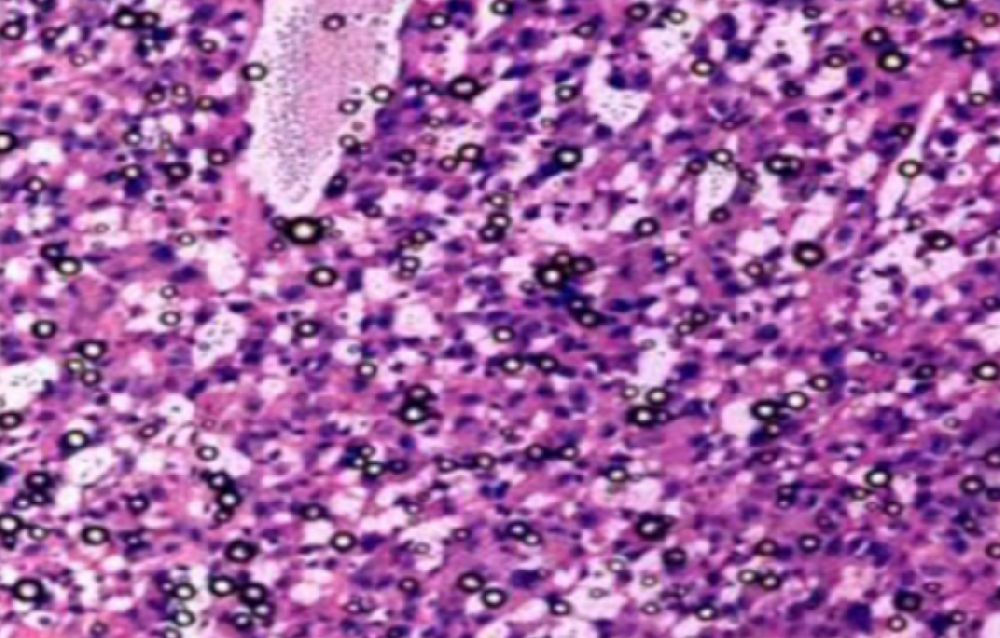

①常规HE染色,切片厚度需要根据不同组织类型而定。

②光镜下首先区分有否特异性病变及范围,然后由脏器一端向另一端进行整体观察和描述。

③观察小动物脏器有否肿大、增生,用10倍镜由一端开始计数该脏器包含的10倍镜镜头视野数,或计数整个切片中功能单位数。如脾生发中心、胸腺小叶、肝小叶、肾小球及整个切片中病变灶数量。

④大动物脏器疑有肿大、增生时,用40倍镜头计数每一视野中的细胞或功能单位数。心肌、骨骼肌在与长轴平行的切面上计数每一视野直径中的肌纤维数、肝小叶中肝细胞索数(数40倍镜视野的一半)。根据需要计数10~20个40倍镜视野。

⑤确定病灶大小后用40倍镜头进行观察。先将镜头的圆周与观察的病灶边缘相切,再观察该病灶在这一视野中的比例。